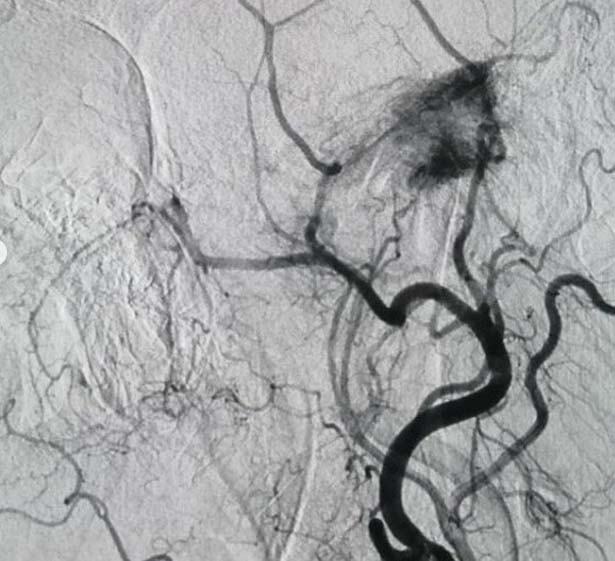

Bülent Ecevit Üniversitesi Uygulama ve Araştırma Merkezi Gelişimsel Radyoloji Doktor Öğretim Üyesi Yaşar Türk, Açıkçası hocamızın değerlendirdiği ve bizlere yönlendirdiği Glomus Tümörü ender görünen tümörlerden bu tümör bizim bölümümüzde doğru tanı koyulduktan sonra hocamızla konuştuk ve işlem öncesi embolisazyon dediğimiz damar yatağını kurutma işlemi yapılabilir mi diye konuştuk. Bunun için önce tanısal anjiyo yaptık. Bu vasküler tümörün bu tümörün yerini, nereden beslendiğini belirledikten sonra mikrobilyalar dediğimiz 300 mikron çapında tıkaçlarla bunları başka damarlara zarar vermeden bu tümörü devre dışı bıraktık. Hem hastamız hem de hocamız için bir konfor sağladık” şeklinde konuştu.